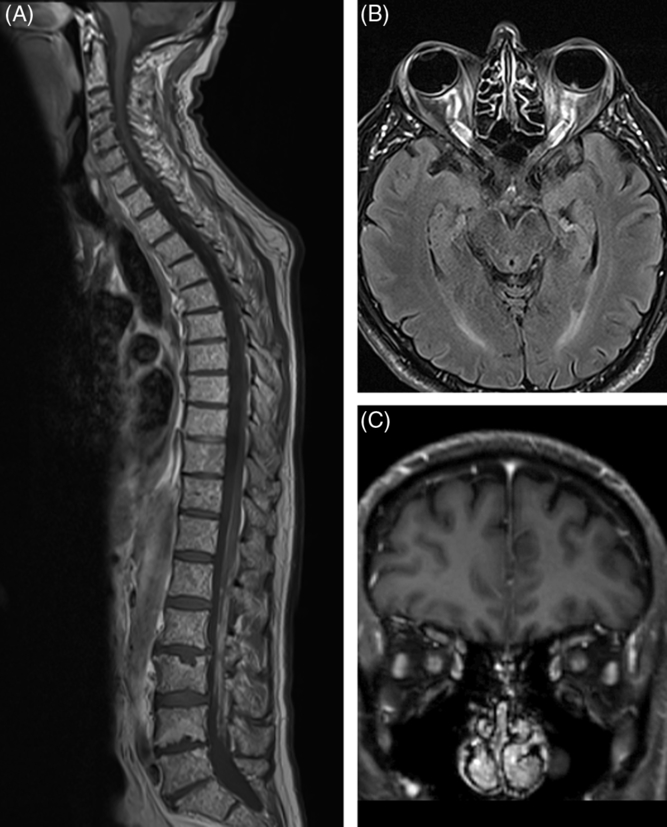

Repeat MRI of the brain demonstrated dilated optic nerve sheaths bilaterally consistent with papilledema but was otherwise unremarkable. Magnetic resonance venography to rule out dural sinus thrombosis due to underlying hypercoagulable state and CT scan of the chest and a Doppler ultrasound of the neck veins to rule out superior vena cava obstruction as a cause of papilledema were performed and were both unremarkable. An LP was repeated demonstrating an elevated opening pressure of 28 cm of water with white cell count of 41, protein of 14,000 mg/L (normal up to 600 mg/L) and again negative cytological analysis for malignant cells. Because of the dramatically elevated cerebrospinal fluid (CSF) protein level, the suspicion for leptomeningeal carcinomatosis (LC) was high. MRI of the spine was performed and demonstrated leptomeningeal metastasis to the surface of the spinal cord and roots of the cauda equina (Figure 2A). Third brain MRI demonstrated diffuse enhancement of leptomeninges surrounding both optic nerves suggestive of metastatic deposits (Figure 2B,C). This leptomeningeal enhancement was not appreciated on both previous MRIs which were done in two separate institutions and interpreted by two different neuroradiologists. Palliative radiotherapy to the spine and orbits commenced and chemotherapy was resumed. Despite treatment, the patient died 3 months after LC was diagnosed; autopsy was declined by the family thus pathological confirmation of the leptomeningeal metastasis was not possible.

Figure 2: (A) Sagittal T1-weighted post-contrast MRI of the spine demonstrating diffuse small metastases throughout the vertebral bodies and linear enhancement along the surface of the spinal cord and roots of the cauda equina. (B, C) Axial and coronal post-contrast T1-weighted views demonstrating enhancement of both optic nerves.

Our patient was found to have bilateral optic nerve head swelling which was initially presumed to be caused by papilledema due to increase in CSF viscosity. However, severely constricted visual fields and the presence of diffuse leptomeningeal thickening and enhancement surrounding intraorbiral optic nerves on imaging suggested bilateral optic neuropathy due to compression of the optic nerves by metastatic deposits as an additional mechanism of optic nerve swelling. The presence of papilledema was supported by relative preservation of central visual acuity despite long-standing disk edema as well as an elevated opening pressure on LP. There are several proposed mechanisms for increased intracranial pressure in patients with LC: it may be secondary to high levels of CSF protein due to leptomeningeal seeding by cancer cells which increases CSF viscosity and leads to its decreased outflow. Another possibility is cerebral edema secondary to increased cerebral vascular endothelial permeability due to aberrant stimulation of the meninges by tumor cells causing release of various chemical mediators Reference Nayar, Ejikeme and Chongsathidkiet6 . Lastly, tumor cells may directly block arachnoid granulations, the presumed main site of CSF absorption.

Second mechanism for marked bilateral disk edema in our patient was most likely a superimposed bilateral optic neuropathy as demonstrated by constricted visual fields and slowly deteriorating central visual acuities. This was most likely secondary to infiltration of subarachnoid space around the optic nerves by malignant cells causing compression of the optic nerves. This process is more plausible as opposed to direct infiltration of the optic nerve by cancer cells, which typically produces very quickly deteriorating vision resulting in catastrophic visual loss.